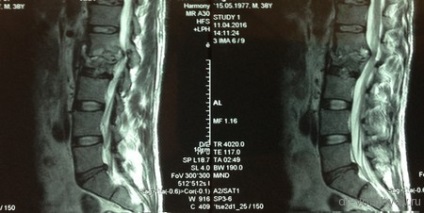

După un curs de detoxifiere și terapia masivă cu antibiotice pacientul a fost pregătit pentru o intervenție chirurgicală. Sa decis să efectueze îndepărtarea corpurilor vertebrale L1 L2 și discul între ele, iar placa corporodesis Masham umplut de os proprii (în acest caz, o margine) în China. Cel mai adesea, atunci când aveți nevoie pentru a manipula 1 vertebre vom trata accesul antero lateral deasupra sau dedesubtul diafragmei. În această situație, operarea cu cotorul de tranziție care implica doua fuziune vertebre apare între TN12 și L3, în total 4 trebuie să expună o vertebră și, prin urmare, a trebuit să folosească TORAKOFRENOLYUMBOTOMIYU. Accesul de-a lungul marginii cu deschiderea cavității pleurale și disectia retroperitoneale și diafragmei pe dreptul său semiperimetrul.

stadiu vizibil de funcționare după instalarea plasei între corpurile vertebrale. Operarea peste toracostomie placa spondylosyndesis (care a fost distrusă după ce a suferit purulent pleurita).

La filmele de control după implanturi chirurgie bună stare, decompresie este realizată în mod adecvat.